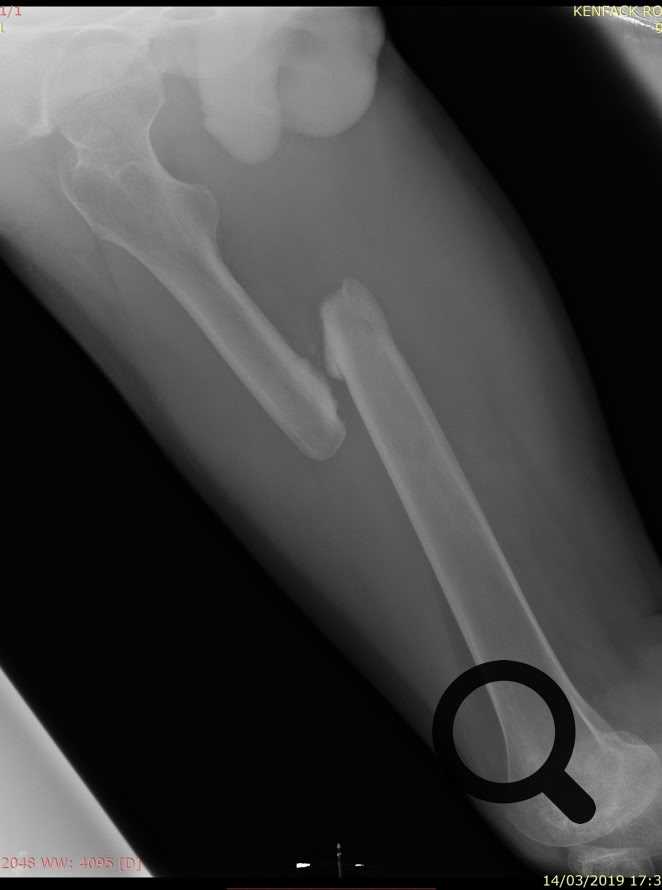

Como no podía ser de otra manera porque nos pasa siempre, nos hemos enfrentado a cirugía de alta complejidad, pseudoartrosis de húmero, fémur y tibia en adultos, así como  fracturas complejas.

Una cosa queda clara, los “masajes tradicionales cameruneses“ no son efectivos en el tratamiento de las fracturas de cualquier hueso, tanto en niños como en adultos y conducen inevitablemente a pseudoartrosis  muy difíciles de tratar.